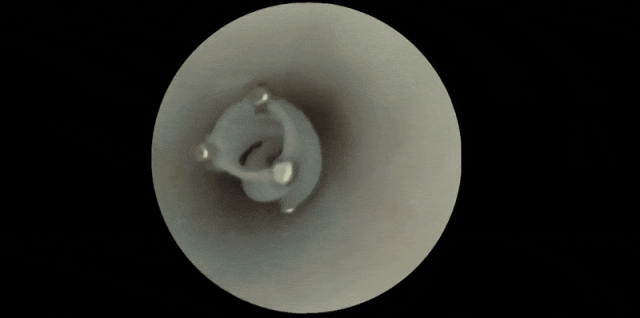

新型微型机器人在脑血管模型(上图)与猪颈动脉(下图)中穿行 | 参考文献